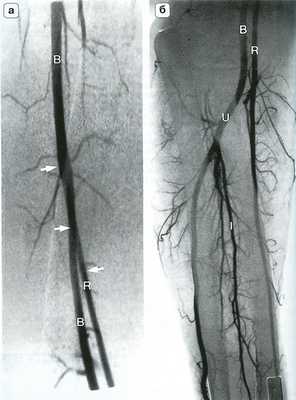

![Рис. 14.4. Артериальная анатомия (а) и костные ориентиры (б) локтевого сустава]()

Рис. 14.4. Артериальная анатомия (а) и костные ориентиры (б) локтевого сустава. Плечевая артерия (В) делится на уровне локтевого сустава на лучевую (R) и локтевую (U) артерии. Межкостная артерия (I) является ветвью локтевой артерии, которая в некоторых случаях продолжается на кисть. RR - лучевая возвратная артерия; UR - локтевая возвратная артерия.

![Рис. 14.6. Высокое отхождение лучевой артерии. На ангиограмме плеча (а)]()

Рис. 14.6. Высокое отхождение лучевой артерии. На ангиограмме плеча (а) и предплечья (б) представлен вариант высокого отхождения плечевой артерии (R - стрелки) на уровне средней трети плеча. В - плечевая артерия; I - межкостная артерия; U - лучевая артерия